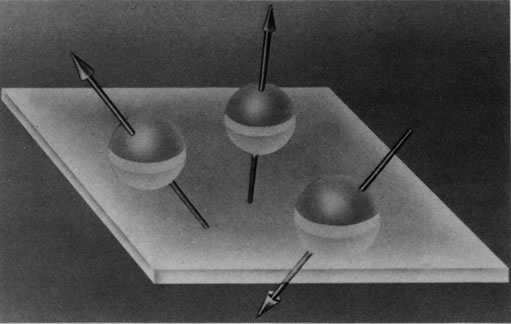

Hydrogen, which contains a single proton, has the largest magnetic moment of all stable atomic nuclei and is highly prevalent throughout biologic tissues. For these reasons, hydrogen forms the basis for MRI and exemplifies its principles. In nature, the magnetic moments of the hydrogen nuclei in biologic tissues are randomly oriented and therefore exhibit no net magnetic effect (Fig. 2). When these nuclei are placed in a strong static magnetic field, such as that produced in an MRI unit, they line up parallel or antiparallel to the field. Slightly more align parallel to the main magnetic field, because this is a lower energy state, and produce a net magnetic vector in this direction (Fig. 3).1,5,8